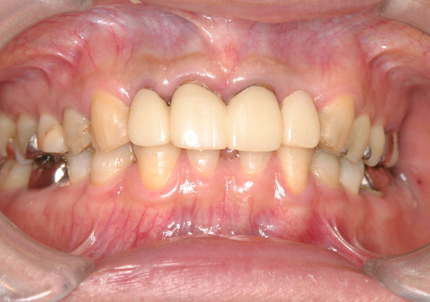

24.口腔内写真

【 2018年 術前 】

【 2025年5月 現在 】